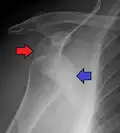

Anterior (forward)

In over 95% of shoulder dislocations, the humerus is displaced anteriorly.[8] In most of those, the head of the humerus comes to rest under the coracoid process, referred to as sub-coracoid dislocation. Sub-glenoid, subclavicular, and, very rarely, intrathoracic or retroperitoneal dislocations may also occur.[9]

Anterior dislocations are usually caused by a direct blow to, or fall on, an outstretched arm. The person typically holds his/her arm externally rotated and slightly abducted.[10]

A Hill–Sachs lesion is an impaction of the head of the humerus left by the glenoid rim during dislocation.[6] Hill-Sachs deformities occur in 35–40% of anterior dislocations. They can be seen on a front-facing X-ray when the arm is in internal rotation.[11] Bankart lesions are disruptions of the glenoid labrum with or without an avulsion of bone fragment.[12]

An anterior dislocation of the shoulder